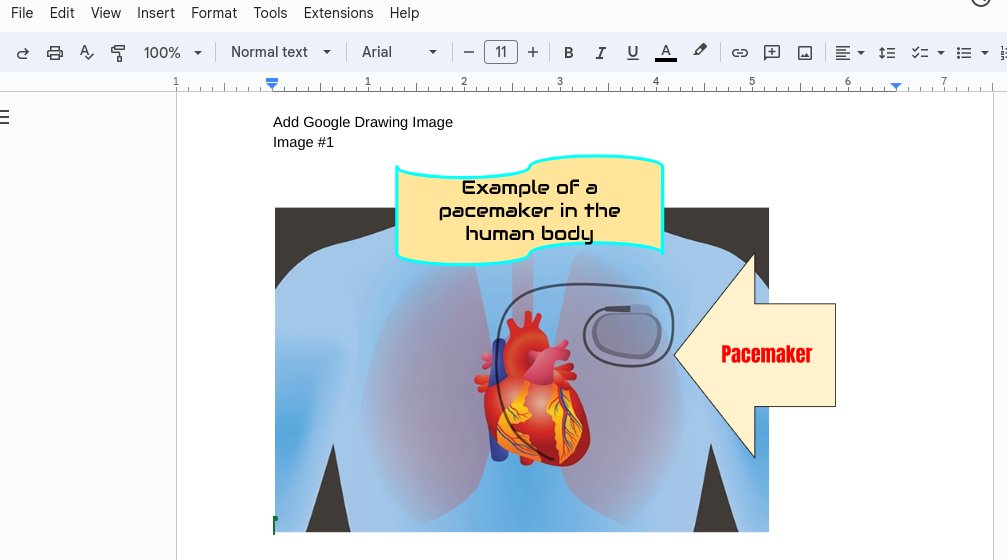

Here is RC teaching 4th grade peers about DIAGRAMS👍🏻 📓💻Ss made digital & paper diagrams! 👓 Take a look @ how one student explored #GoogleDrawing to add labels to a hockey rink diagram.